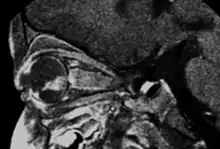

Inherited forms of retinoblastomas are more likely to be bilateral. In addition, inherited uni- or bilateral retinoblastomas may be associated with pineoblastoma and other malignant midline supratentorial primitive neuroectodermal tumors (PNETs) with a dismal outcome; retinoblastoma concurrent with a PNET is known as trilateral retinoblastoma.[15] A 2014 meta-analysis showed that 5-year survival of trilateral retinoblastoma increased from 6% before 1995 to 57% by 2014, attributed to early detection and improved chemotherapy.[16]

In about two-thirds of cases,[27] only one eye is affected (unilateral retinoblastoma); in the other third, tumors develop in both eyes (bilateral retinoblastoma). The number and size of tumors on each eye may vary. In certain cases, the pineal gland or the suprasellar or parasellar region (or in very rare cases other midline intracranial locations) is also affected (trilateral retinoblastoma). The position, size, and quantity of tumors are considered when choosing the type of treatment for the disease.

If the eye examination is abnormal, further testing may include imaging studies, such as computerized tomography (CT), magnetic resonance imaging (MRI), and ultrasound.[28] CT and MRI can help define the structure abnormalities and reveal any calcium depositions. Ultrasound can help define the height and thickness of the tumor. Bone marrow examination or lumbar puncture may also be done to determine any metastases to bones or the brain.

Drawing of a large retinoblastoma Aspect of trilateral retinoblastoma on MRI

Traditional ultrasound B scan can detect calcifications in the tumour while high-frequency ultrasound B scan is able to provide higher resolution than the traditional ultrasound and determine the proximity of the tumour with front portion of the eye. MRI scan can detect high-risk features such as optic nerve invasion; choroidal invasion, scleral invasion, and intracranial invasion. CT scan is generally avoided because radiation can stimulate the formation of more eye tumours in those with RB1 genetic mutation.[35]